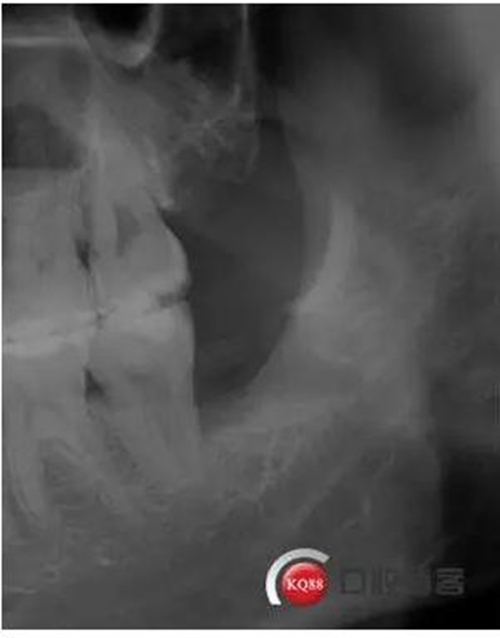

檢查:口內(nèi)可見(jiàn)38未完全萌出,無(wú)松動(dòng),周?chē)例l顏色正常,叩診(—)觸診(—),X線(xiàn)顯示近中阻生,雙根

處理:治療計(jì)劃及費(fèi)用已說(shuō)明,知情同意后,排除拔牙禁忌癥:口腔黏膜消毒,左下頜阻滯麻醉成功后,切開(kāi)翻瓣,渦輪機(jī)去除近中阻力,向近中挺出患牙,拼對(duì)牙體完整,清創(chuàng),置明膠海綿,縫合傷口,咬棉球壓迫止血